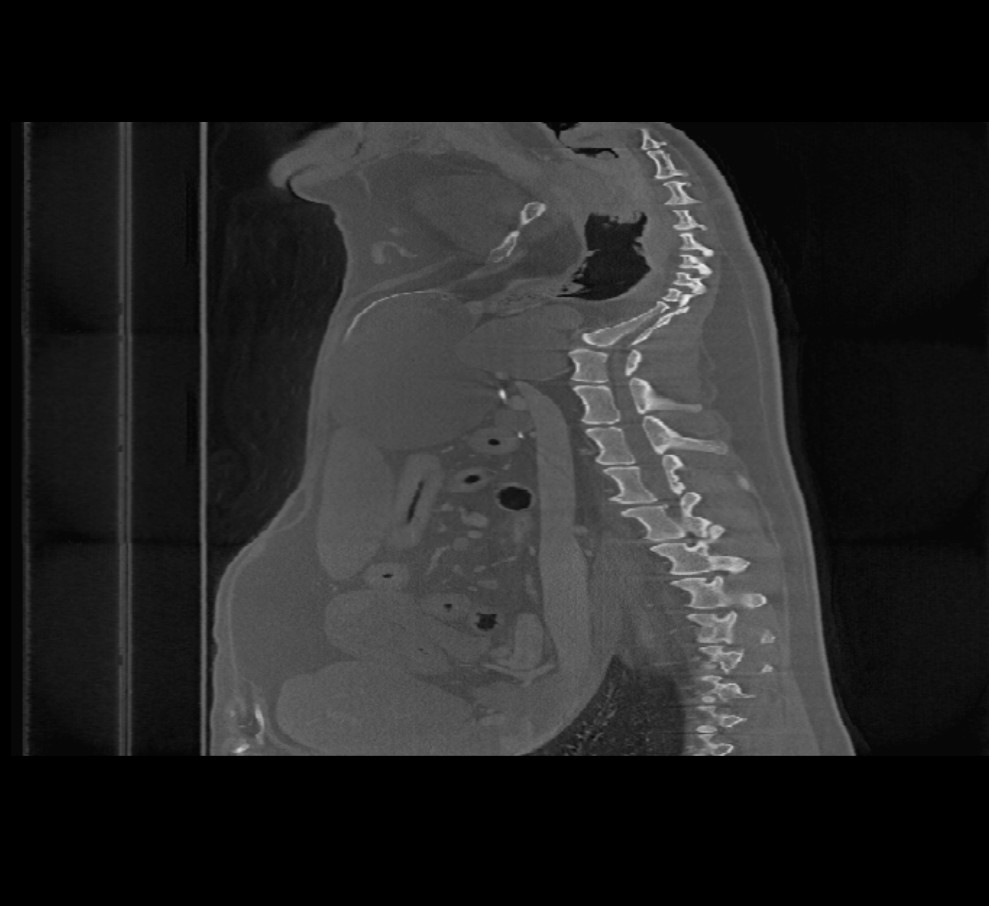

Beim Öffnen volumetrischer DICOM-Bilder im Viewer (CT- und MR-Modus) steht in der oberen Symbolleiste ein zusätzliches Menü mit dem Titel Bildebenen zur Verfügung. Ändern Sie die Ausrichtung des Bildes, indem Sie eine der drei verfügbaren Ebenen auswählen (Axial, Koronal und Sagittal).

Die gewählte Ebene beeinflusst die Position und Ausrichtung der CT-/MR-Schnitte sowie deren Rekonstruktion auf der 2D-Ebene.